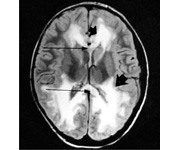

vascular dementia microscopic findings

Front

extensive atherosclerotic or hypertensive microvascular changes hyaline arteriolosclerosis lipohyalinesclerosis

Back

vascular dementia gross findings

cerebral atrophy and ex vacuo hydrocephalus from reduction in white matter multifocal lacunar infarcts